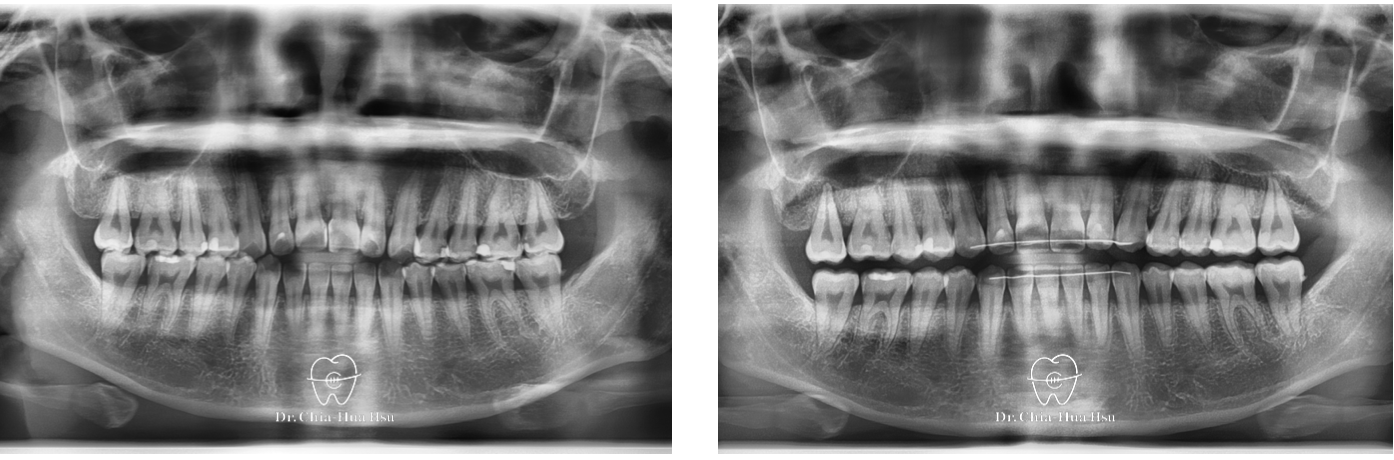

開咬

成人矯正 | 金屬矯正 | 非拔牙治療

• 病患主訴:從小就前牙開咬,不論是美觀或進食上都困擾許久。

• 問題分析:患者是骨骼一類咬合(Skeletal Class I)合併前牙開咬。

• 治療方式:使用自鎖式金屬矯正器,配合齒間鄰接面修磨,再搭配齒間橡皮筋的使用,使開咬順利解決。另外,也有教導患者正確的舌頭擺放位置與運動練習。

• 治療時間:9個月。

• 治療結果:咬合恢復正常,微笑曲線更自然!

治療前

治療後